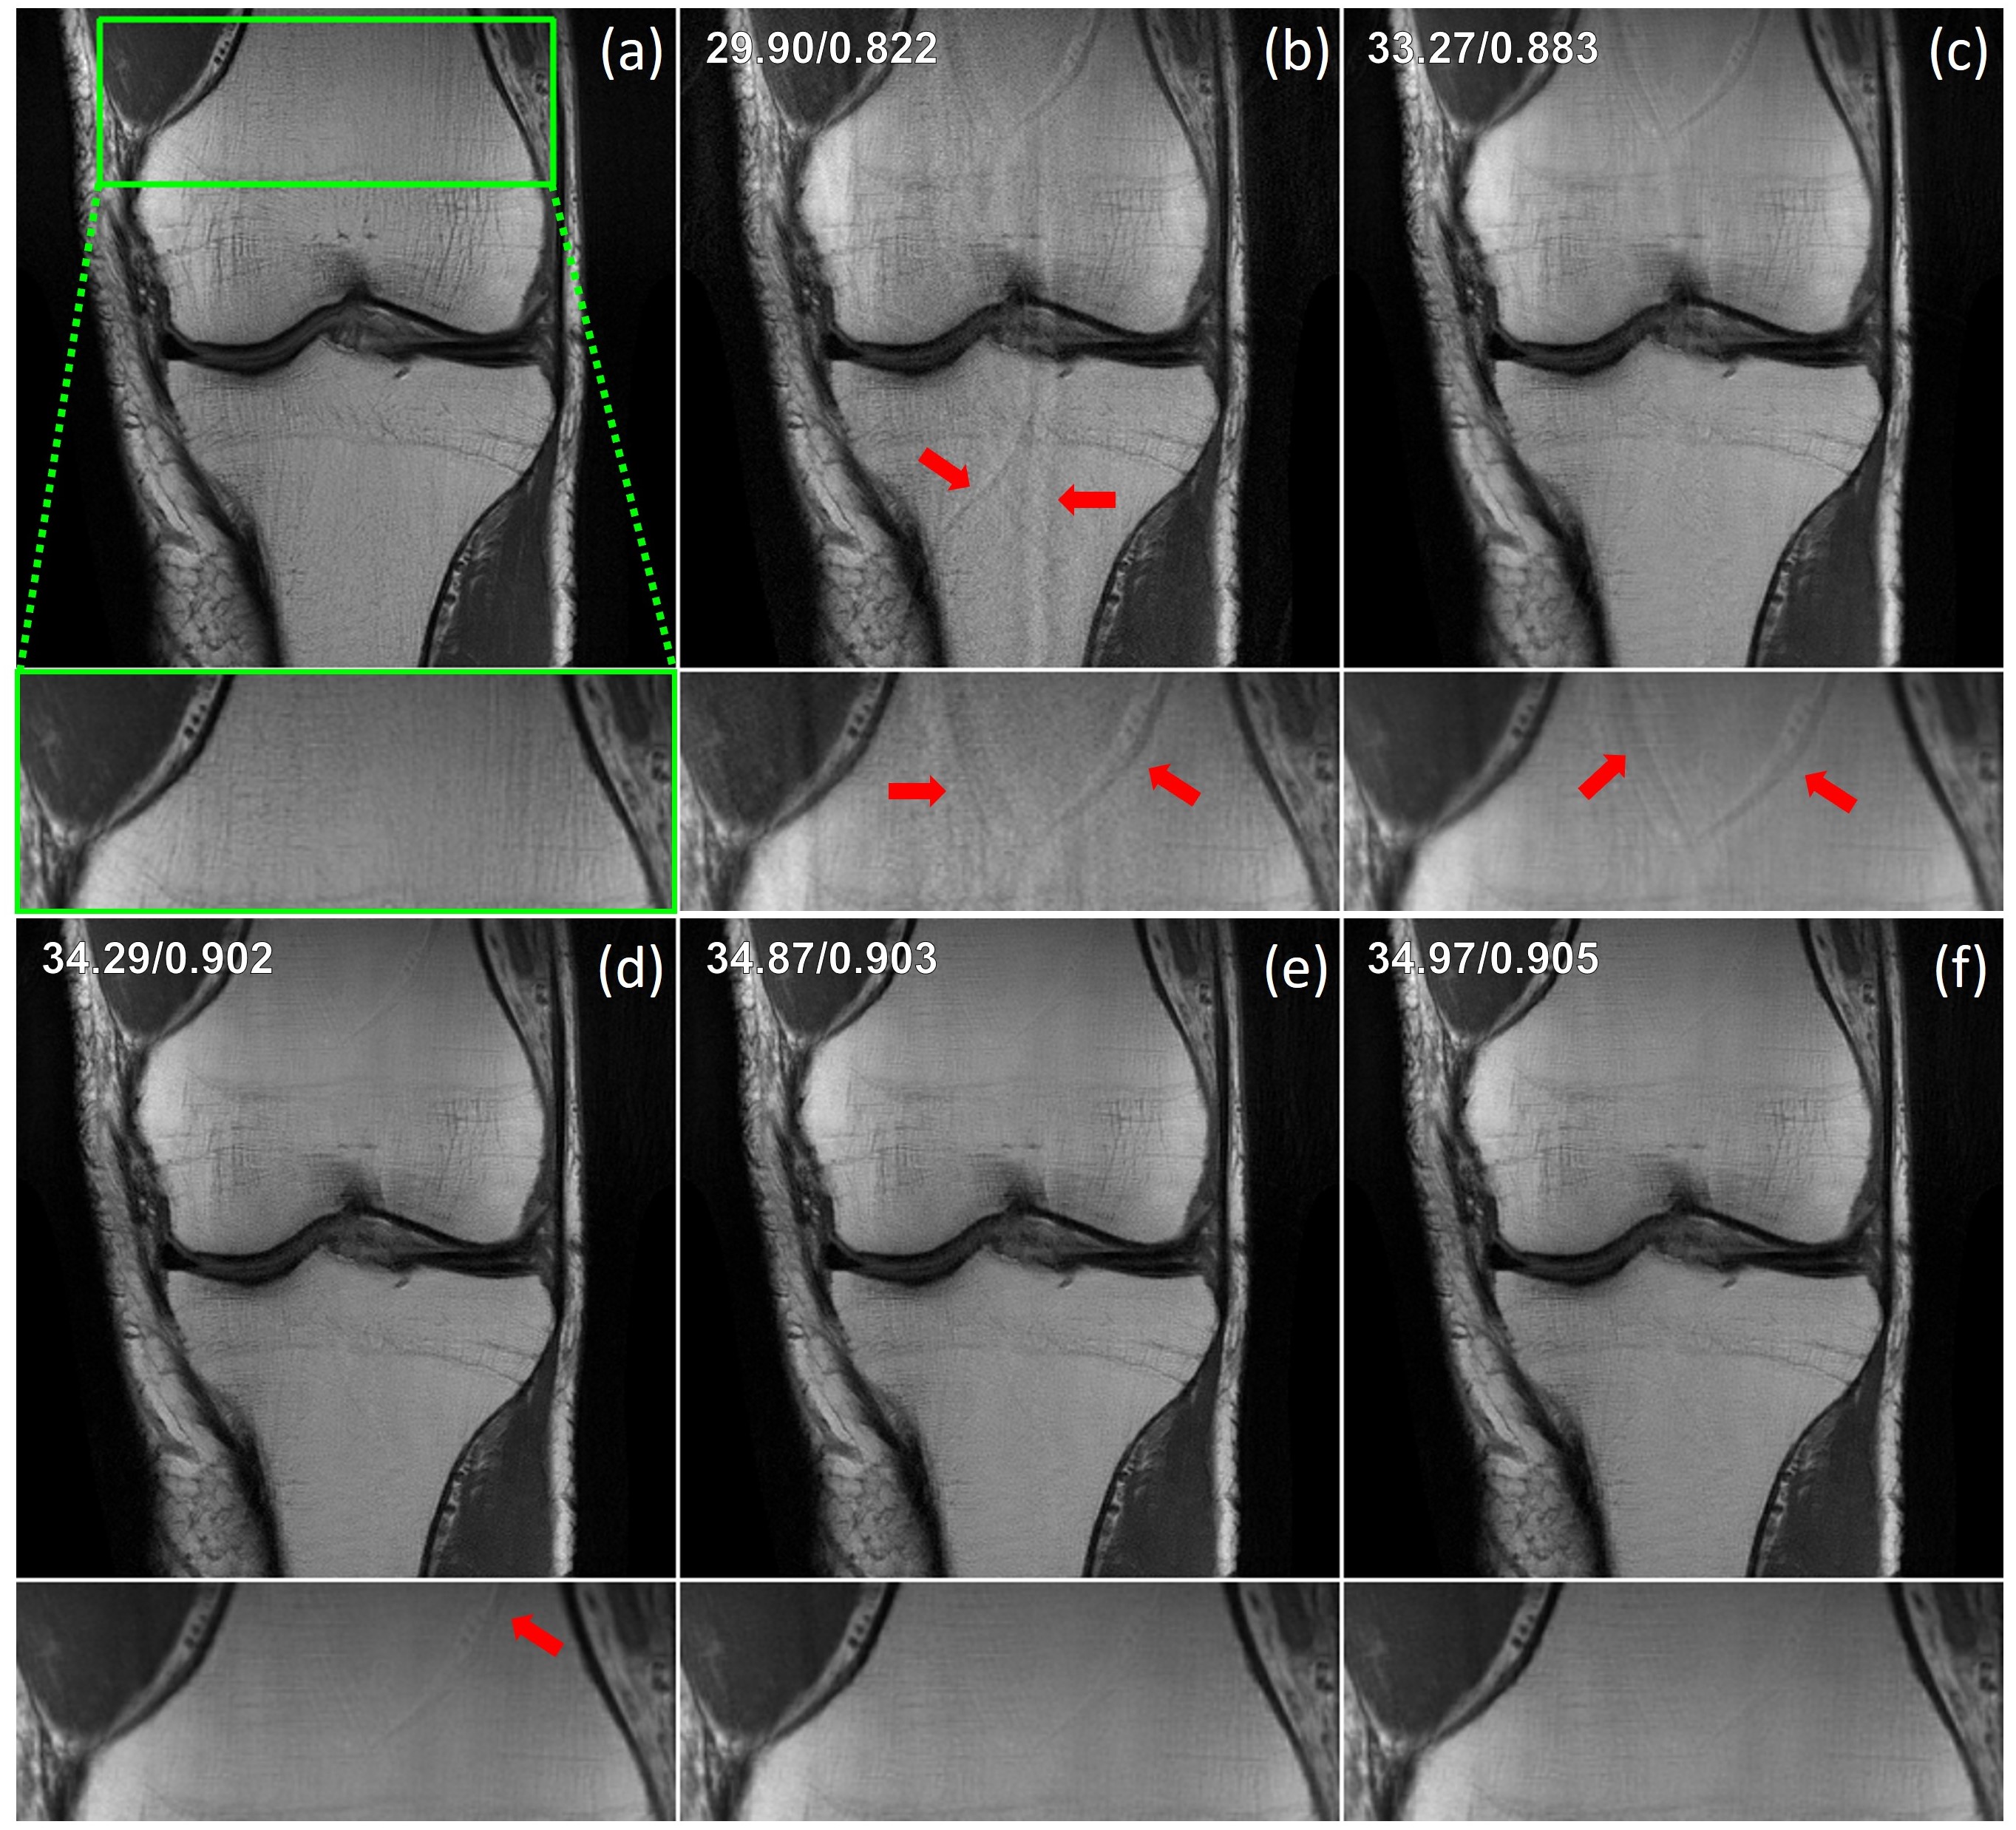

Refer to caption

Figure 3: Representative slices reconstructed at an acceleration factor of R=4R=4 using equidistant undersampling from coronal PD and coronal PD-FS knee MRI, as well as axial T2-weighted brain MRI. The baseline CG-SENSE, CS, EI-trained PD-DL, and DDS suffer from residual artifacts highlighted by red arrows. PD-DL trained with CUPID improves upon them while delivering reconstruction quality comparable to supervised and SSDU-trained PD-DL.

Representative results in Fig. 3 show that baseline CG-SENSE, CS and EI reconstructions exhibit residual artifacts, whereas DDS suffers from minor noise amplification. In contrast, CUPID successfully eliminates these artifacts from the CG-SENSE image using a well-trained PD-DL network, achieving a state-of-the-art reconstruction quality comparable to supervised PD-DL and SSDU, despite only having access to 𝐱PI{\bf x}_{\textrm{PI}} for training, and not to raw k-space data unlike these other methods. We observe that parallel imaging reconstruction is not clinically usable at higher acceleration rates, but is improved using a CUPID-trained PD-DL reconstruction. Quantitative results in Tab. 4.2 support visual observations, showing that CUPID consistently outperforms CG-SENSE, CS, and EI across multiple datasets. It also outperforms ScoreMRI and DDS across various scenarios in the majority of cases, while achieving performance comparable to supervised PD-DL and SSDU, both of which have access to raw data. Further qualitative results are provided in Appendix I.